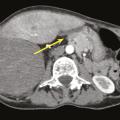

Radiothérapie dans le traitement des sarcomes

Depuis les années 1980, la chirurgie conservatrice suivie d’une radiothérapie postopératoire est devenue le standard thérapeutique pour la plupart des sarcomes des tissus mous des membres.1,2 Le bénéfice de l’association radio-chirurgicale est surtout observé chez des patients avec des tumeurs de haut grade, de localisation profonde…